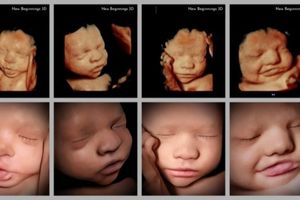

تشخیص بارداری: سونوگرافی یکی از روشهای استاندارد برای تأیید بارداری است. در این روش میتوان سن بارداری، تعداد جنینها، موقعیت جنین و وجود یا عدم وجود مشکلاتی مانند حاملگی خارج از رحم را بررسی کرد.

بررسی رشد و سلامت جنین: سونوگرافی در طول بارداری برای بررسی وضعیت رشد جنین، سلامت قلبی-عروقی آن و بررسی مشکلات احتمالی مانند نقصهای مادرزادی استفاده میشود.